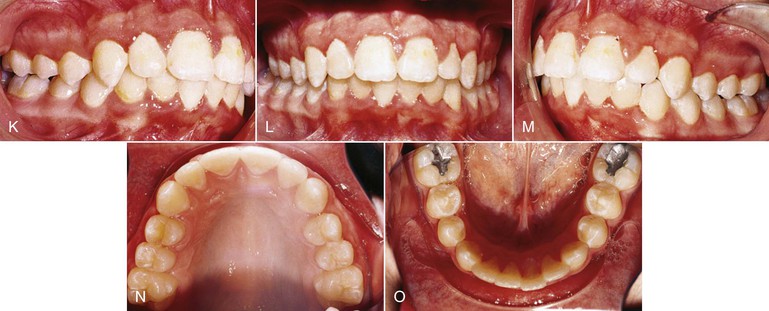

Though initially recommended for use in combination with headgear, we have noted that the VHA on its own is useful for correction of Class II malocclusion. Figure 12-4 documents a patient whose initial treatment plan was for treatment with a straight-pull facebow headgear, but she declined to use it. The patient was put under observation for 6 months while the VHA was cemented to the maxillary first molars. A fixed lingual arch (FLA) was also cemented to the mandibular arch for maintenance of the leeway space. Even though the leeway space may not always be available,19 the FLA can be used to control the vertical dimension during the growth period.20 After 6 months, correction of the Class II malocclusion was observed. No other appliance was used during this period.

Figure 12-4 Class II, Division 1 malocclusion treated with a vertical holding appliance (VHA). A–E, Pre-treatment intraoral photographs of a Class II, Division 1 subdivision left malocclusion. F–J, Progress photographs showing a VHA cemented to the maxillary first molars and a fixed lingual arch (FLA) cemented to the mandibular first molars. These photographs were taken 6 months after delivery of the VHA and FLA. K–O, Final records at completion of treatment.